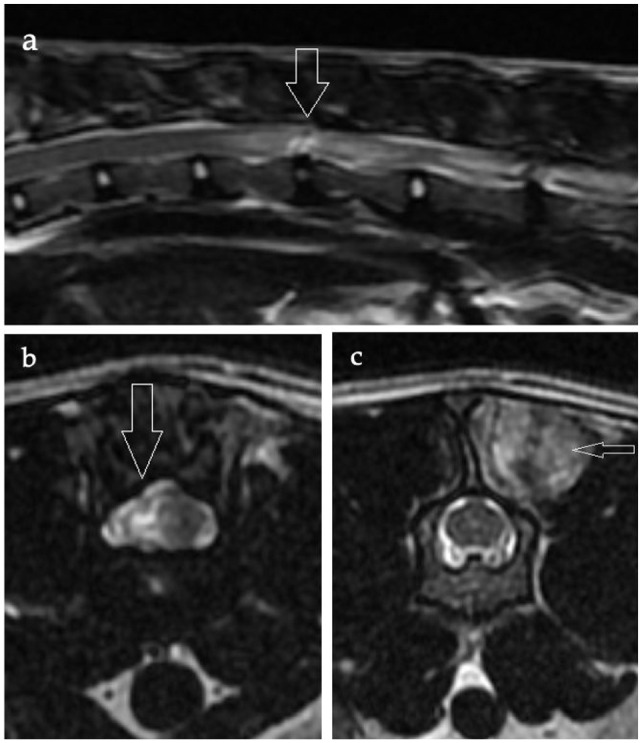

目的本研究旨在描述推测诊断为髓内椎间盘突出症的猫的临床特征、MRI表现、治疗和预后。方法回顾性分析诊断为髓内椎间盘突出症的猫的病历和MRI资料。通过医疗记录、由患者完成的问卷或两者同时评估长期结果(大于或小于6个月)。结果12只猫符合纳入标准。所有患者均表现出过急性或急性临床症状,其中9例患者根据病史、体格检查或MRI表现证实(n = 3)或可能(n = 6)有外伤。7只猫是活动的,5只猫是非活动的。8只猫出现尿失禁;没有一例出现大便失禁。神经解剖定位包括T3-L3 (n = 7)和L4-S3 (n = 5)脊髓节段。MRI显示以下部位的椎间盘突出:T12-T13 (n = 1), T13-L1 (n = 1), L1-L2 (n = 2), L2-L3 (n = 2), L4-L5 (n = 3)和L5-L6 (n = 3)。所有猫均接受治疗,中位住院时间为4天(范围3-14天)后出院。所有有随访信息的不能活动的猫(4/5)在短期(

ObjectivesThis study aimed to describe the clinical characteristics, MRI findings, treatment and outcome in cats presumptively diagnosed with intramedullary intervertebral disc extrusions.MethodsA retrospective review was conducted of medical records and MRI data from cats presumptively diagnosed with intramedullary intervertebral disc extrusions. Long-term outcome (⩾6 months) was assessed through medical records, questionnaires completed by the owners or both.ResultsA total of 12 cats met the inclusion criteria. All presented with peracute or acute clinical signs, with nine having confirmed (n = 3) or possible (n = 6) external trauma based on history, physical examination or MRI findings. Seven cats were ambulatory and five were non-ambulatory. Eight cats presented with urinary incontinence; none exhibited faecal incontinence. Neuroanatomical localisation included the T3-L3 (n = 7) and L4-S3 (n = 5) spinal cord segments. MRI showed an intramedullary intervertebral disc extrusion at the following sites: T12-T13 (n = 1), T13-L1 (n = 1), L1-L2 (n = 2), L2-L3 (n = 2), L4-L5 (n = 3) and L5-L6 (n = 3). All cats underwent treatment and were discharged after a median hospitalisation time of 4 days (range 3-14). All non-ambulatory cats with available follow-up information (4/5) regained ambulation by the time of the short-term (<6 weeks) or long-term (⩾6 months) assessment. Moreover, all cats either retained or regained urinary continence by the time of discharge, the short-term (<6 weeks) or the long-term (⩾6 months) assessment. Overall, nine cats achieved a successful outcome and were considered functional pets at the short-term (<6 weeks) and/or long-term (⩾6 months) follow-up. Two cats were lost to follow-up, and one cat had perceived persistent generalised discomfort.Conclusions and relevanceMost cats presumptively diagnosed with an intramedullary intervertebral disc extrusion showed a favourable outcome with treatment in this study. This condition should be considered in cats presenting with peracute or acute signs of T3-L3 or L4-S3 spinal cord dysfunction, especially if there is a history or indication of trauma.